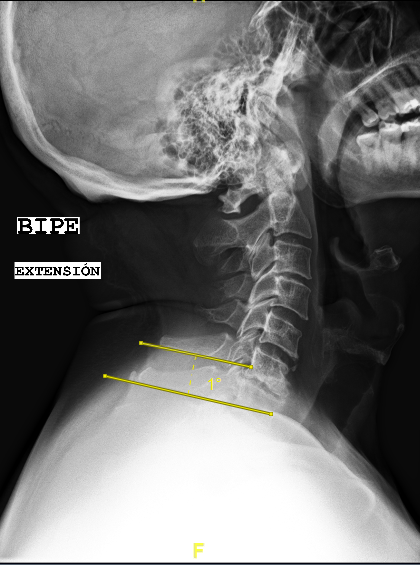

Las RX dinámicas reflejan la ausencia de fusión C6-C7